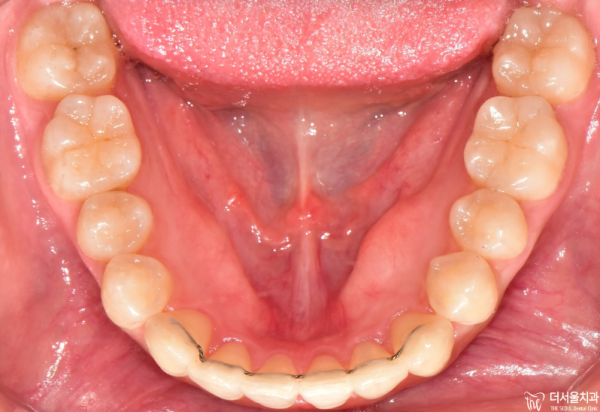

이렇게 교합면을 보면 앞니들이 위 아래 모두 삐뚤빼뚤한

총생을 보이고 있습니다.

If you look at the occlusal side, the front teeth are all crooked.

He's living his whole life.